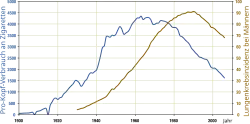

Mit einem zeitlichen Versatz von 20 bis 30 Jahren verlaufen die beiden Kurven parallel verschoben.

Die Hauptursache bei der Entstehung des Tumorleidens ist der Tabakrauch. Er enthält etwa 2000 Stoffe, von denen mindestens 100 krebserregend (karzinogen) sind (beispielsweise Teer und eine Vielzahl anderer Kohlenwasserstoffverbindungen). Es wurde nachgewiesen,[11] dass das im Tabakrauch enthaltene Benzo[a]pyren das als Tumorsuppressor bekannte Protein p53 schädigen kann. 95 Prozent aller Patienten mit Bronchialkarzinom sind Raucher oder ehemalige Raucher. 30 bis 40 Jahre nach Beginn des Rauchens ist das Erkrankungsrisiko bei starken Rauchern bis zu 60-fach höher als beim Nichtraucher. Auch Passivraucher atmen dieselben Stoffe wie Raucher ein, allerdings in vielfach geringerer Konzentration. Das Risiko für Nichtraucher, die dauerhaft dem Passivrauch ausgesetzt sind, ist mit dem 1,2 bis 1,3-fachen gegenüber nicht exponierten Nichtrauchern deshalb nur moderat erhöht.[12][13] Die sogenannte British Doctors Study belegte schon in den 1950er Jahren den Zusammenhang zwischen Lungenkrebs und aktivem Rauchen. Die Wahrscheinlichkeit, bis zum 75. Lebensjahr an Lungenkrebs zu erkranken, liegt bei Männern, die ihr gesamtes erwachsenes Leben geraucht haben, bei 1:6. Bei Männern, die bis zum Lebensalter von 60, 50, 40 und 30 Jahren das Rauchen aufgegeben haben, liegt die Wahrscheinlichkeit bei 1:10, 1:16, 1:33 und 1:50. Bei Männern, die nie geraucht haben, liegt die Wahrscheinlichkeit nur bei ca. 1:250.[14] War das Bronchialkarzinom im Jahr 1913, mit 337 in der gesamten Literatur beschriebenen Fällen, noch ein „sehr seltener Tumor“[15], so gab es 2008 seinetwegen weltweit etwa 1,38 Millionen Sterbefälle.[16] In Ländern wie den USA, wo der Anteil der Raucher bereits seit den 1960er Jahren wieder sinkt, stellt sich nun auch ein deutlicher Rückgang an Lungenkrebserkrankungen ein, der mit einem zeitlichen Versatz von 20–30 Jahren nahezu parallel zum Rückgang des Tabakkonsumes verläuft.